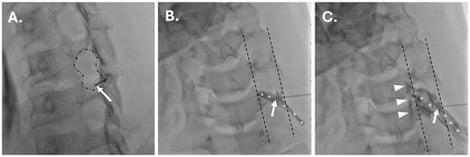

Background/Objectives: Fluoroscopically guided cervical nerve root corticosteroid injections are used for the treatment and diagnosis of radicular pain. Including a local anesthetic with the injected corticosteroid may decrease the pain associated with the procedure and add immediate diagnostic value. However, little is known about the safety of including a local anesthetic with a corticosteroid in these injections. Methods: A total of 299 consecutive cervical nerve root injections, performed between 2016 and 2024, were reviewed. Demographic and injection information (level/laterality and inclusion/exclusion of 1% preservative-free lidocaine with dexamethasone injectate) were documented. Charts were reviewed for major complications and increased pain post-procedure. Categorical data were compared between groups using Fisher’s exact test or Chi-square testing. Results: Injections were performed with 10 mg of dexamethasone only in 263 cases and with a mixture of 10 mg of dexamethasone and 1 mL of 1% lidocaine in 36 cases. There was no statistically significant difference in the incidence of major complications (p ≈ 1) or immediately increased pain post-procedure (p = 0.799). Conclusions: With proper technique, there is no evidence from this case–control study or in the available literature to suggest that including lidocaine with corticosteroid increases risks associated with cervical nerve root injections. However, serious adverse events are theoretically possible with injection of local anesthetic into a radicular artery, the vertebral artery, or subdural space. Given that such risks are not associated with the use of non-particulate steroids alone, large multi-institutional studies are needed to draw confident conclusions on the risks and benefits of the inclusion of local anesthetics with non-particulate corticosteroids for cervical transforaminal epidural steroid injection to inform clinical practice.